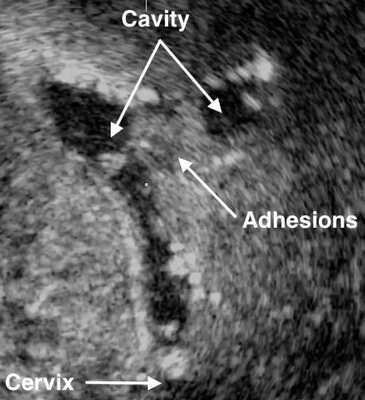

- Ультразвуковое исследование. Если есть спайки, то на снимках видны эхогенные, нерегулярные эксцентричные линейные сигналы — беловатые плотные участки рубцовой ткани или локальное истончение эндометрия. Исследование проводят в лютеиновую фазу (период с момента овуляции и до начала менструаций).

Гистероскопия является самым точным и надёжным методом диагностики синдрома Ашермана . Другие техники выполняют вспомогательное значение и часто дают противоречивые результаты при субмукозных миомах (узлах, растущих в полость матки) и при гиперпластических процессах эндометрия.